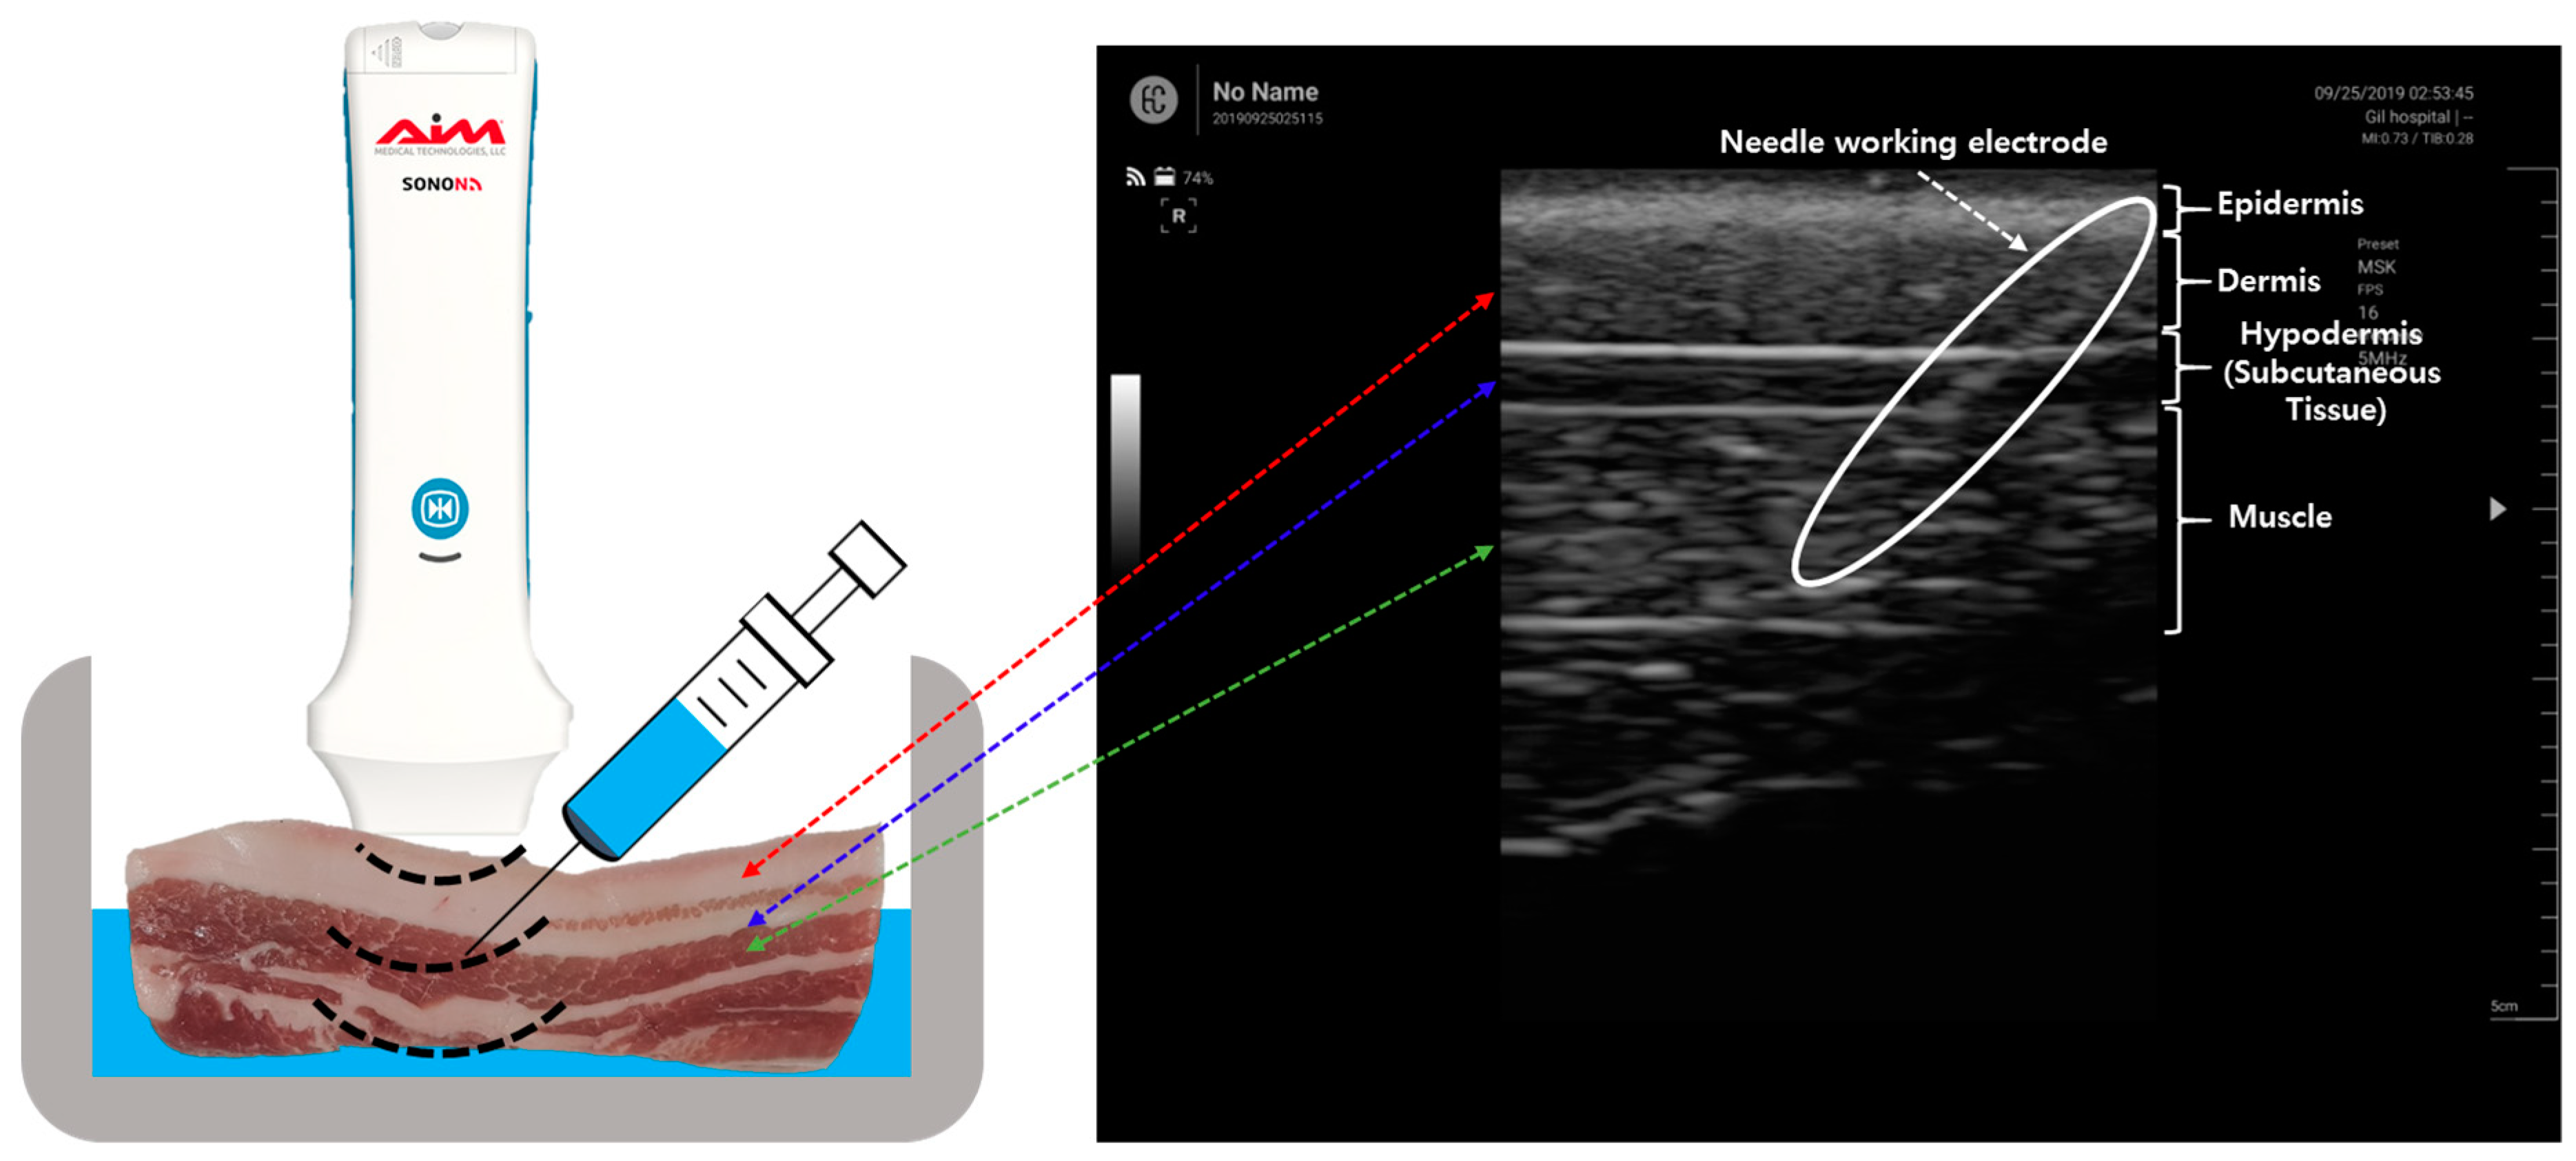

The pork bellies from a 6-month-old mixed-breed pig were purchased from a butcher shop in the city of Seongnam, Korea and immediately taken to the laboratory over ice crystals to avoid the degradation of tissue. A piece of porcine skin composed of skin, dermis, hypodermis, and muscle was purchased and immersed in a saline (0.9% NaCl) solution to maintain the water content in tissue and the electrical conductivity of the tissue during the experiment. The porcine skin had the size of 150 mm (length) × 40 mm (width) × 50mm (height), and the weight of 0.3 kg. The experiment setup of the LIA-based impedance measurement system for detection of the tip position of the monopolar injection needle (25 gauge, Chalgren Enterprises, Inc., Gilroy, CA, USA) in the tissue layers with the Ag/AgCl counter electrode and saline injection with the syringe pump and ultrasound device is shown in Figure 1. The monopolar injection needle had an insulated outer wall with an outer diameter of 0.51 mm, an inner diameter of 0.26 mm, and a length of 50 mm. The monopolar injection needle was inserted into the pork tissue from the skin and positioned at a single tissue layer at a time with the help of US (SONON 300C, Healcerion Inc., Seoul, Korea). The electrical impedance spectrum of the pork tissue was measured in the frequency range of 10 Hz to 10 kHz, using the lock-in amplifier-based impedance measurement system and the Ag/AgCl counter electrode, which was placed on the skin of the pork tissue. The electrical impedance of the tissue was monitored, not only during the movement of the monopolar injection needle in the tissue layers, but also during injection of the saline (0.9% NaCl) solution used for arthrocentesis in a certain tissue layer. To avoid the effect of temperature on the impedance measurement of tissues, the temperature was kept constant (22 °C) during the experiment.

Figure 1.

Experimental setup of the lock-in amplifier (LIA)-based impedance measurement system for detection of the tip position of the monopolar injection needle in the tissue layers with Ag/AgCl counter electrode and saline injection with the syringe pump and ultrasound (US) device.

For the electrical impedance measurement of the pork tissue, the monopolar injection needle was positioned at a specific tissue layer using US. Figure 3 shows an ultrasound image of the pork tissue used for the experiment consisting of the epidermis (depth: 0.2 to 0.4 cm), dermis (0.4 to 1.1 cm), hypodermis (1.1 to 1.4 cm), and muscle (1.4 to 2.6 cm).

Figure 3.

Ultrasound image of the needle insertion in the tissue layer.